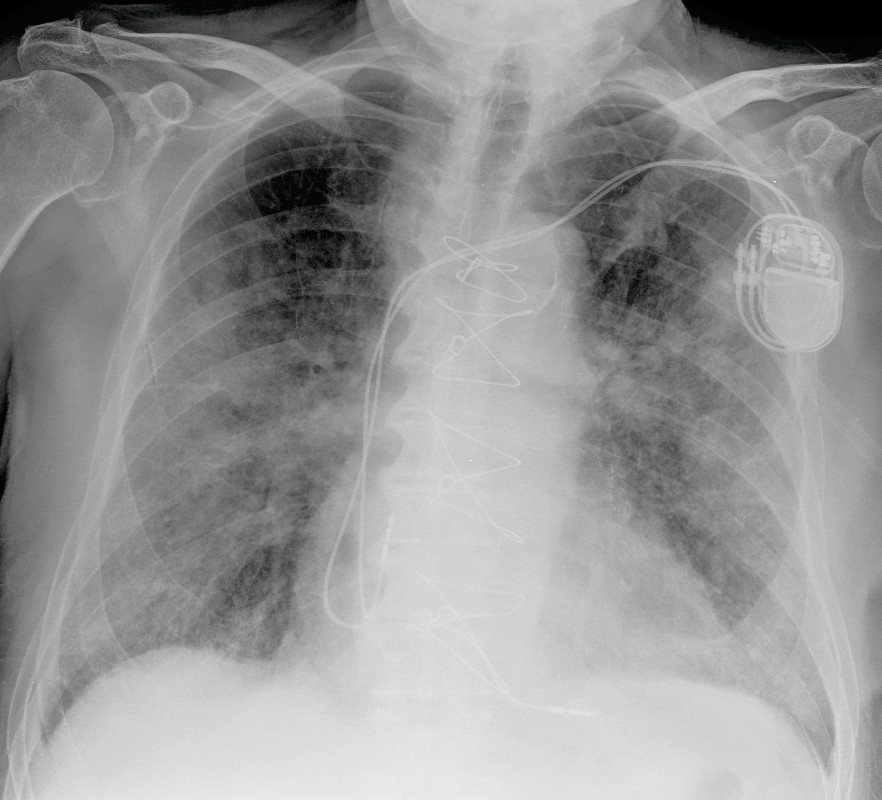

Fastlegen hadde kjent pasienten gjennom mange år. Fra tidligere hadde han hypertensjon, trekar hjertesykdom med gjennomgått nedreveggsinfarkt, kronisk obstruktiv lungesykdom i stadium 2 i henhold til GOLD-kriteriene, og benign prostatahyperplasi. Grunnet AV-blokk grad 2 type 2 med venstre grenblokk hadde han fått implantert en tokammer pacemaker ni måneder før den aktuelle hendelsen. Ekkokardiografi utført i den forbindelse viste god venstre ventrikkel-funksjon uten signifikante klaffefeil. Pasienten gikk jevnlig til kontroller hos fastlegen, og tok sine medisiner som foreskrevet. Han hadde sluttet å røyke for 40 år siden og hadde et lavt alkoholforbruk. Til tross for alvorlige kroniske lidelser var pasienten til vanlig helt selvhjulpen og oppegående og hadde ikke behov for ganghjelpemidler. Han kjørte bil og hadde gjennomført førerkortvurdering med god kognitiv skår. Han var aktiv som frivillig på flere arenaer.

Røntgen thorax viste ikke overbevisende tegn til stuvning, men økende løst mettede fortetninger med økende konsolidering som indikerte sykdomsprogresjon (figur 2). Utover kvelden på sykdomsdag 7 ble han stadig mer besværet i pusten, med respirasjonsfrekvens over 40 per minutt og oksygenmetning ned mot 60 %, til tross for høyt oksygentilskudd på maske med reservoar.

Mens det første røntgenbildet av lungene på sykdomsdag 2 var uten fortetninger, hadde pasienten mattglassfortetninger i alle lungeavsnitt på pulmonal CT-angiografi utført på sykdomsdag 5. Mattglassfortetninger kan sees ved flere tilstander og gjenkjennes ved at forandringene ikke overskygger lungestrukturene. Slike med eller uten konsolidering er beskrevet hos pasienter med covid-19 (11−14). Konsolidering er fortetninger hvor lungens normalanatomi utviskes. CT skal ikke brukes som diagnostisk verktøy eller screeningverktøy, men kan være aktuelt i tilfeller hvor det er mistanke om komplikasjoner som ikke er avklart på røntgen thorax (15). CT kan være mer sensitiv enn rRT-PCR i tidlige stadier av sykdommen og i et epidemisk område, men er ikke spesifikk, og andre interstitielle pneumonier vil kunne gi lignende funn (16)−(17). CT vil for disse pasientene være en meget begrenset ressurs, fordi det må gjøres tidkrevende smittevask av laboratoriet mellom hver undersøkelse. Det ble ikke tatt ny CT i sykdomsforløpet til vår pasient, men på sykdomsdag 7 ble det tatt røntgen thorax som viste økende løst mettede fortetninger med økende konsolidering (figur 2). Dette indikerte sykdomsprogresjon.